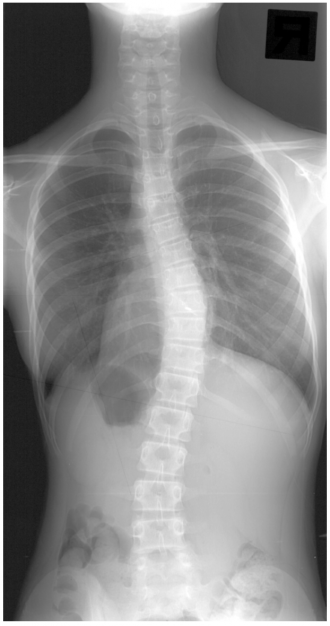

背骨を正面から見ると、背骨はまっすぐになっていますが、側弯症とは背骨がねじれを伴って横に曲がってしまう疾患です。

側弯症の診断は、医療機関を受診し、レントゲン検査を行ってもらう必要があります。